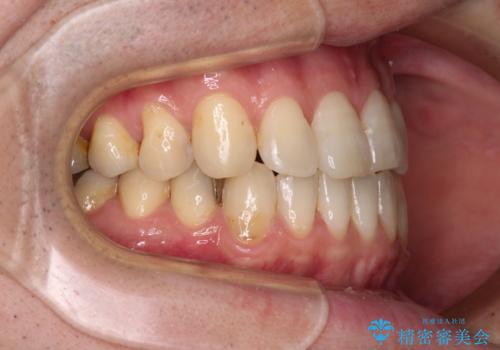

左上の犬歯が欠損しているため、正中の位置や奥歯の咬み合わせが理想的にならない点を了承していただきました。

インビザライン矯正は、1日22時間を目安に装着する必要がありますが、しっかりと装着してくださったので、順調に治療を進めることができました。